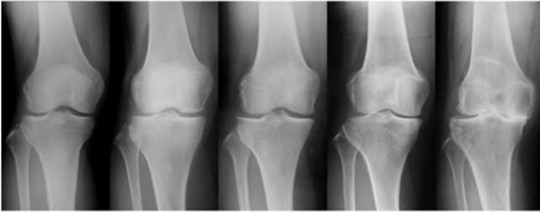

年代ごとの変形の進み具合

左が若い年代で右にいけばいくほど変形が進んでいる

膝関節の問題は年代によって違いがあります。

年代が若い時の膝の悩みは、写真の左側になる。

右側は変形が進み『手術』という言葉が選択肢として出てくる。